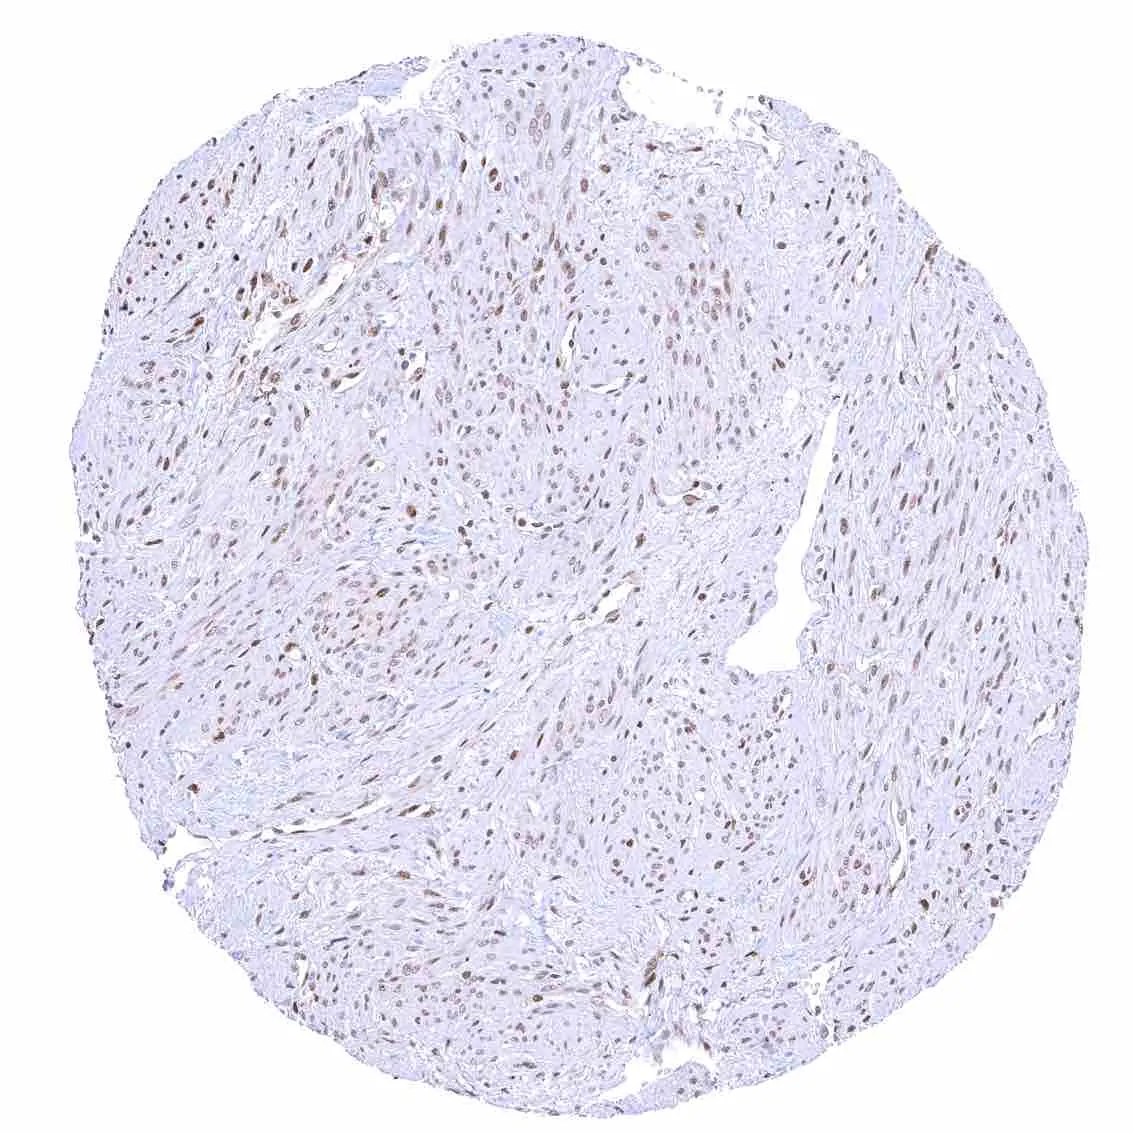

Uterus, myometrium – Nuclear p27 staining of variable intensity in most muscle cells.